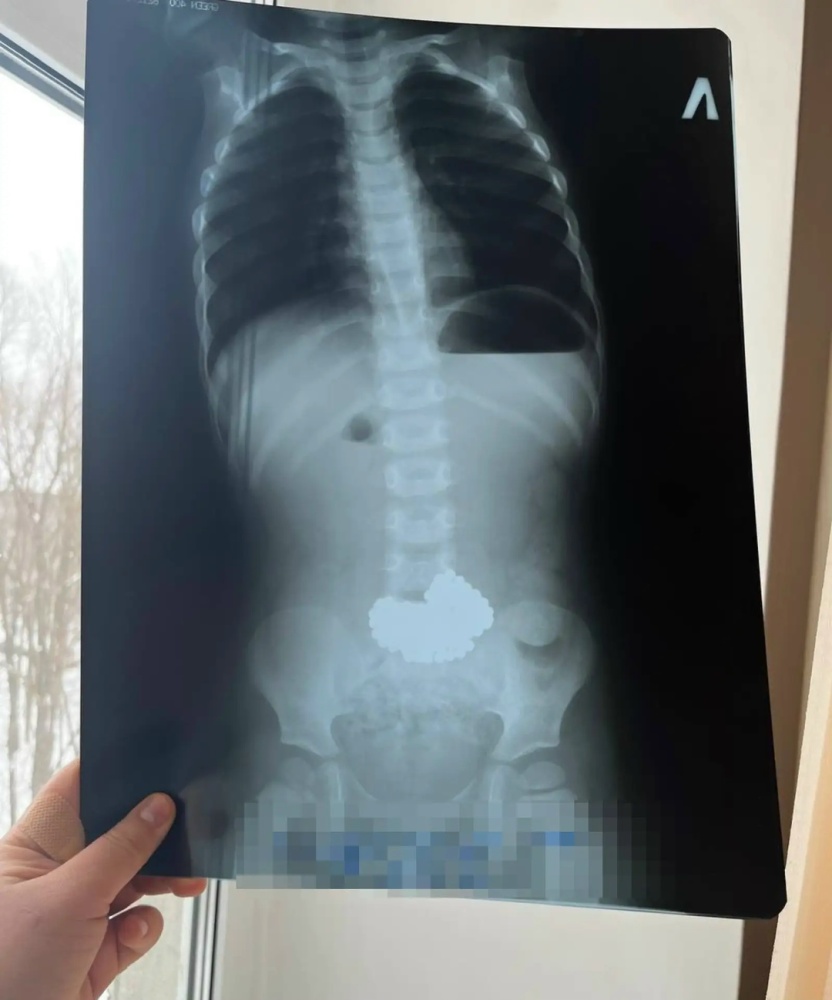

Санитарная авиация доставила маленького пациента в Республиканскую детскую клиническую больницу г.Уфы. Врачи приняли решение об оперативном вмешательстве, во время которого удалили неодимовые шарики-магниты.

Магнитные игрушки при проглатывании могут вызывать тяжелейшие осложнения: некрозы, перфорации и сепсис, который может привести к летальному исходу. Не покупайте детям игрушки с мелкими магнитами, храните подобные предметы в недоступных местах, а при проглатывании немедленно вызывайте скорую помощь Давайте помнить, что здоровье и безопасность наших детей всегда должны быть на первом месте.